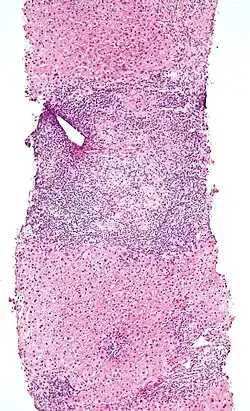

Pathology

An elevated IEL population, as determined by biopsy, typically indicates ongoing inflammation within the mucosa. In diseases such as celiac sprue, IEL elevation throughout the small intestine is one of many specific markers.[1] IELs have heightened activated status that can lead to inflammatory disease such as IBD, promote cancer development and progression,[12] or become the malignant cells in enteropathy-associated T-cell lymphoma, a lymphoma that is a complication of celiac sprue.[13][14]

Alternatively, elevated IEL populations can be a marker for developing neoplasia in the tissue such as found in cervical and prostate cancers, as well as some colorectal cancers, particularly those associated with Lynch syndrome (hereditary non-polyposis colon cancer <HNPCC>).[15] IELs themselves can, when chronically activated, undergo mutation that can lead to lymphoma.[16]